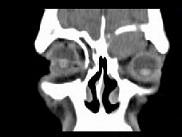

- 单项选择题男,53岁, 近两年来渐进性头痛,伴左眼球外突, 并向前下方移位,CT检查如图, 最可能诊断为 ( )